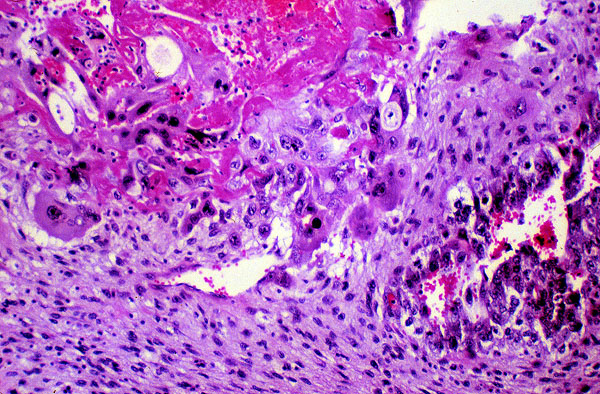

Teratocarcinoma, histology, high power

The tumor is composed of cells that vary in size and shape. The nuclei of these cells seem to overlap and the cell borders are not distinct. There are prominent mitotic figures and some cells appear to have condensed nuclei indicative of apoptosis.